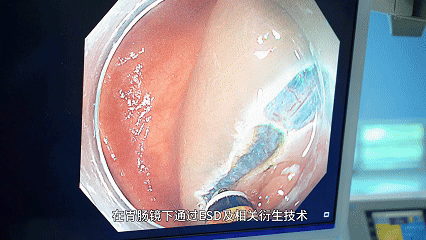

别怕,ESD 技术来「拆弹」!

作为消化道早期肿瘤的「克星」,堪称「超级微创」的代表。

简单说,它不用开腹开刀,医生通过胃肠镜就能把肿瘤组织完整「剥除」—— 就像用精准的手术刀在黏膜上「剥离」病灶,创伤小,术后几天就能正常吃饭。

能最大程度保住消化道的正常功能,完全不影响以后干饭、喝奶茶的快乐~